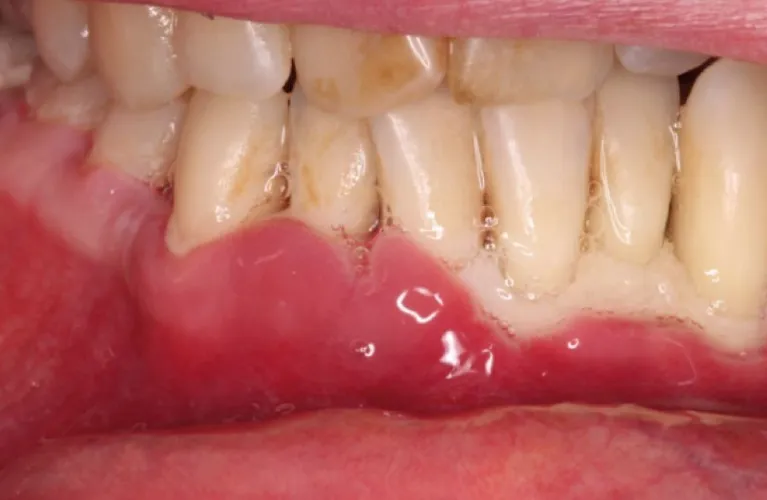

Healthy gums are firm to the touch and fit snugly around your teeth. In comparison, periodontitis has loose teeth and symptoms include:

- Reddish or purplish gums.

- Swollen gums.

- Gums that bleed easily.

- Tender bleeding gums.

- Gum recession (when your gums pull away from your teeth).